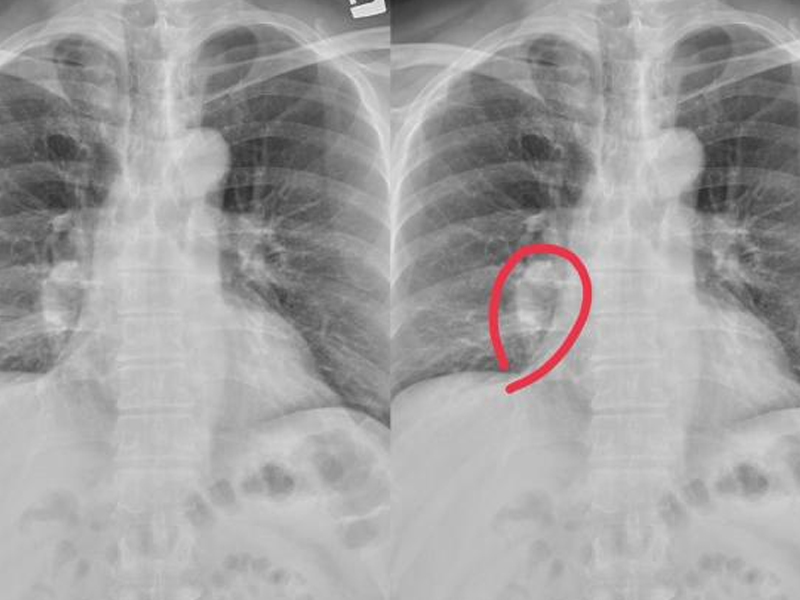

面上若有這 4 種異常,建議查下肝 CT

鼻頭有發紅的現象

肝功能受損也可以觀察一下自己的鼻子部位,也會出現鼻頭髮紅的情況,這也是由於產生肝硬化,從而導致肝功能異常,體內雌激素紊亂,血液中的雌激素含量水平過高。

通過血管運輸到身體各個器官,從而就會導致鼻子上的毛細血管,以及細胞受到一定的刺激,這樣也會產生鼻頭變紅的情況,所以生活中千萬別忽視了這種症狀及,就醫檢查治療。